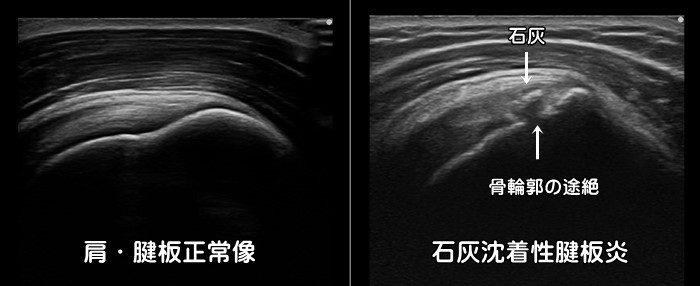

石灰沈着性腱板炎

肩を真横へ上げていく外転動作での痛みが強いのが特徴です。急性型の場合は前日まで全く症状がなく、朝起きると激痛で肩が上がらなくなります。10日前後で痛みは消失しますが慢性型の場合は数年にわたって肩の痛みが続き、年のせいだと石灰沈着に気が付かない場合もあります。好発部位は肩の棘上筋・棘下筋と呼ばれる筋肉内ですが、石灰は体の至る所に沈着します。